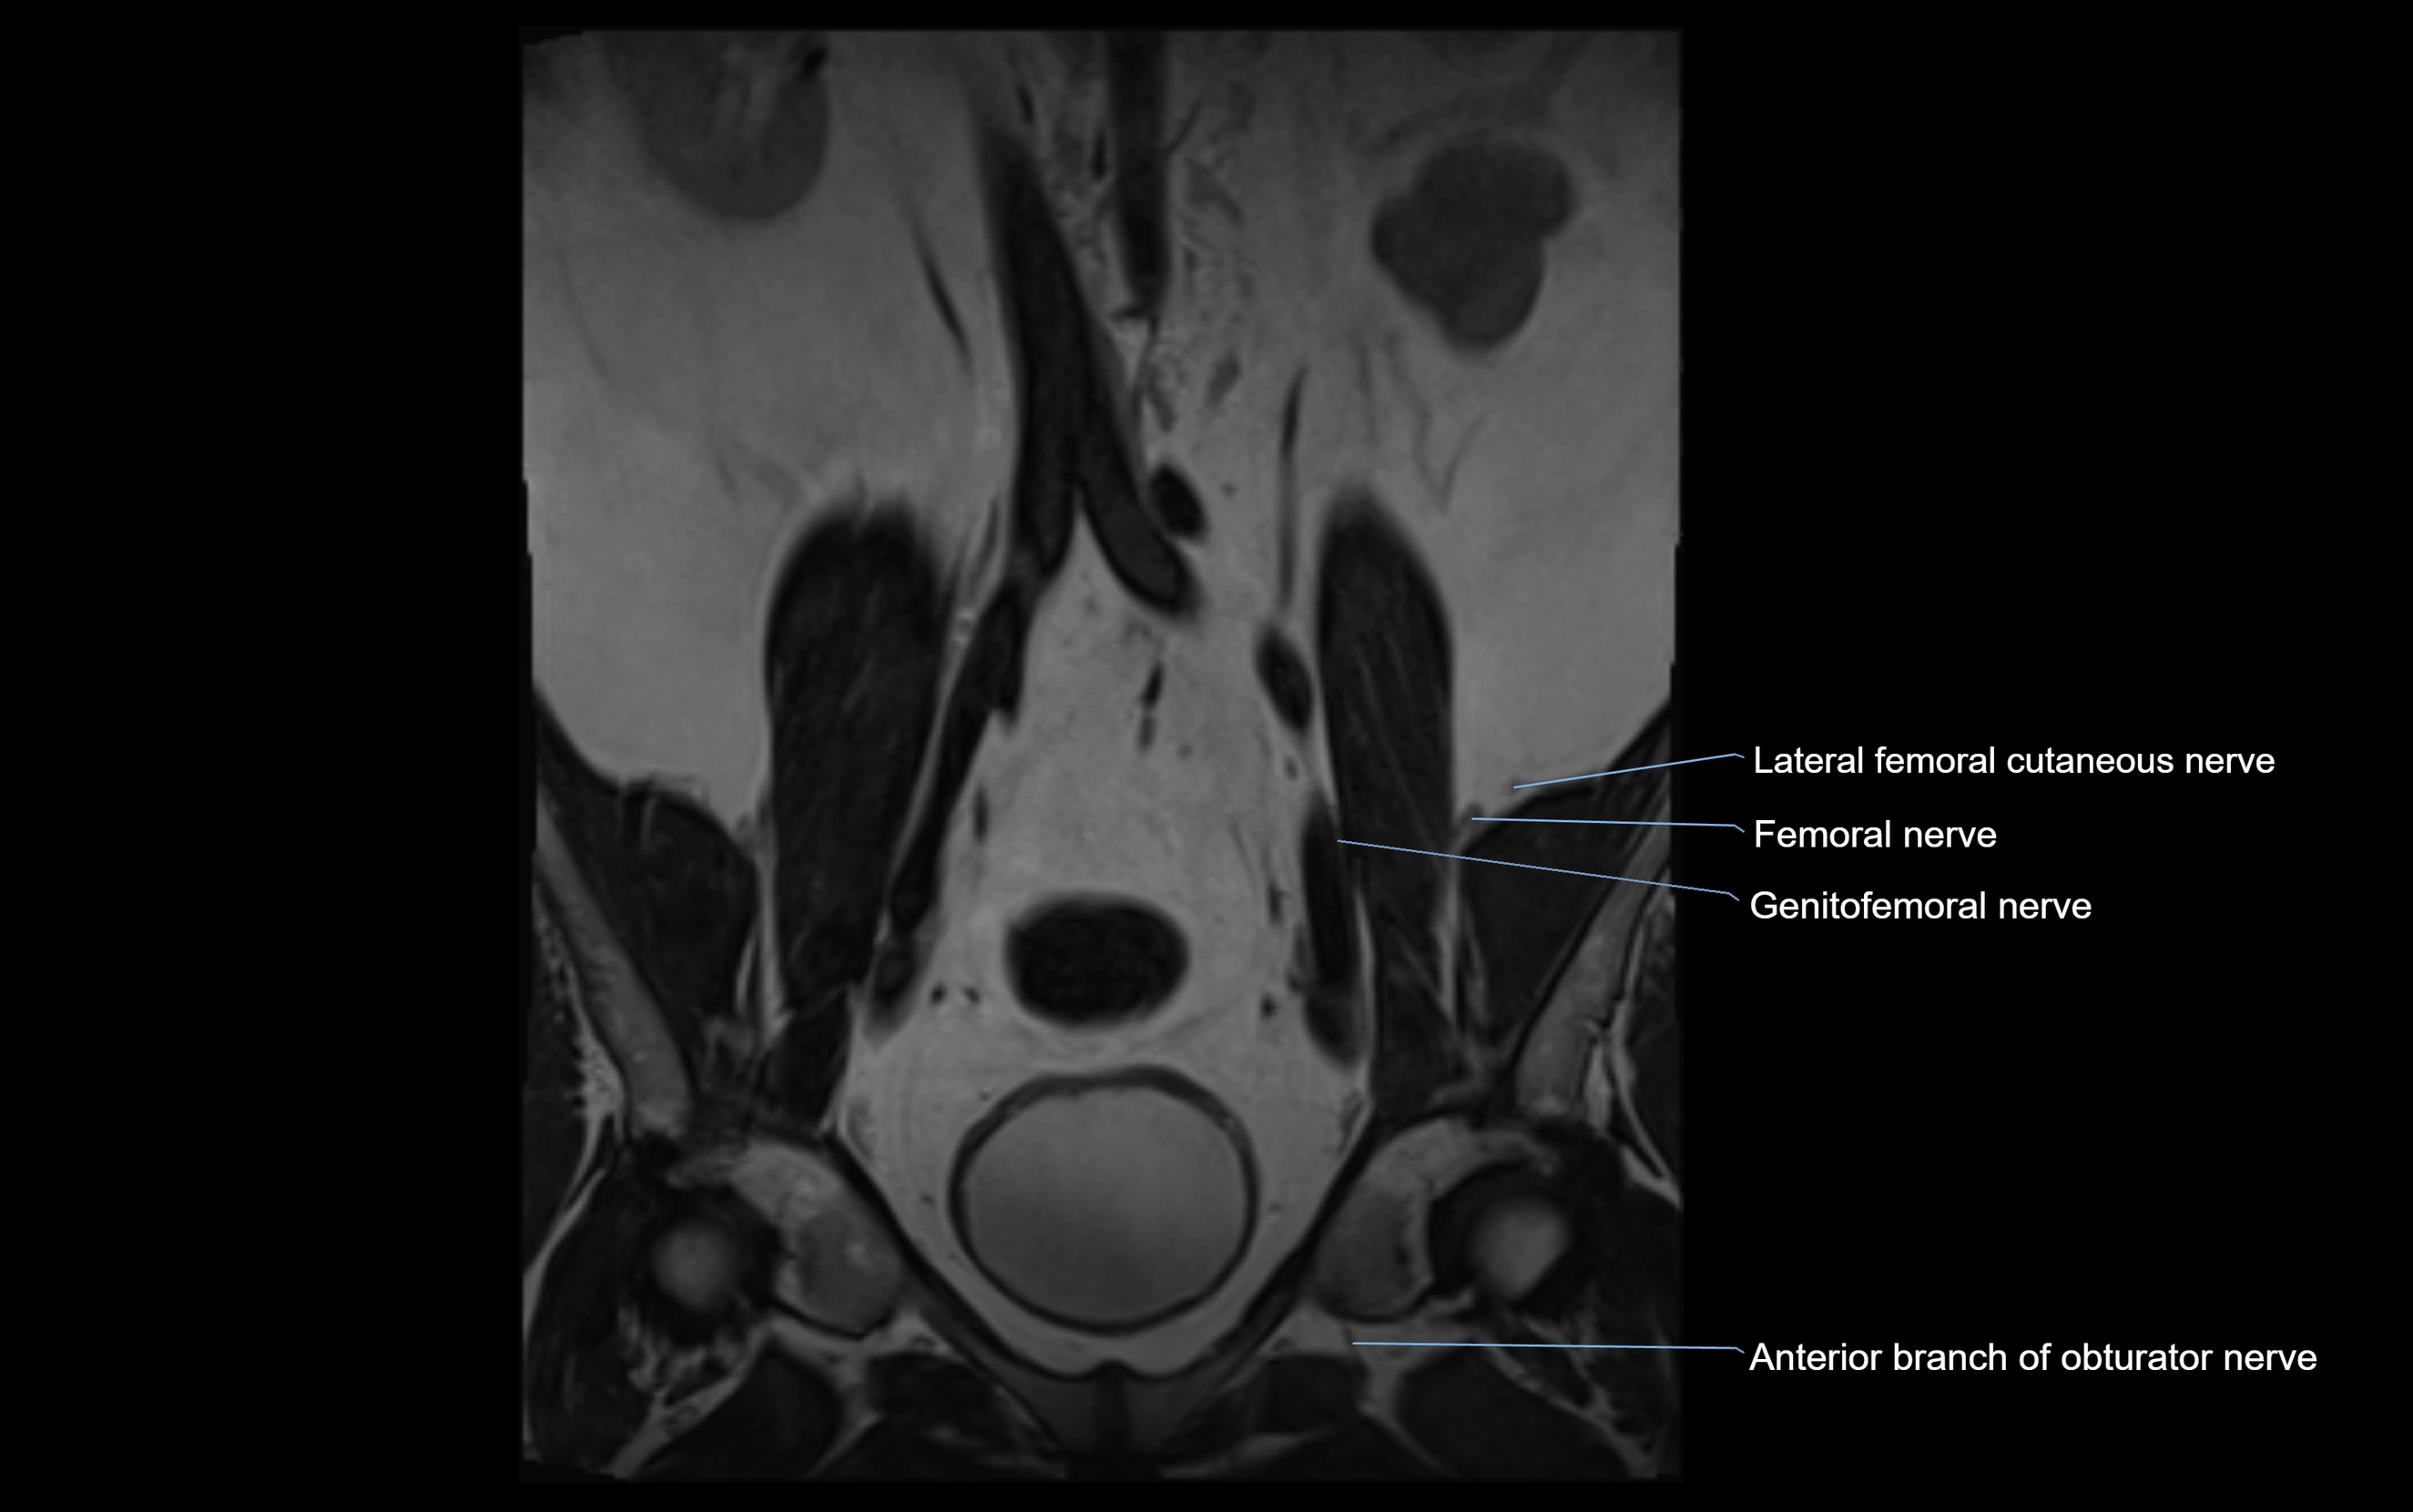

MRI image

image